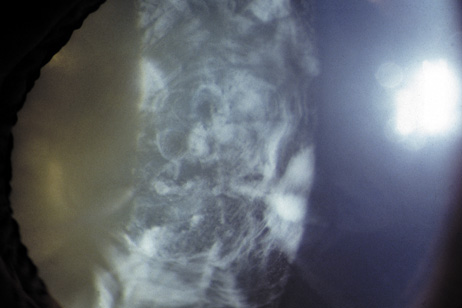

The dense bilateral lens opacities may present as a biconvex-shaped cataract or as posterior, polar, nuclear, or total cataract. The discoid lens shape may result from loss of lens material due to a posterior lens capsule defect4 or defective lens fiber formation and subsequent degeneration.5 The cataracts are present at birth, and glaucoma may be present congenitally or develop within the first 3 years of life. Other ocular findings may include corneal opacity, mitotic pupil, enophthalmos, and hypotonia.6 The cognitive impairment presents with a discrete behavioral phenotype that includes temper tantrums, irritability, complex repetitive behaviors, and unusual mannerisms. Severe renal Fanconi's syndrome may lead to progressive renal impairment. Most boys will develop a distinctive facies and habitus, and attain a height of less than 5 feet because of developmental retardation. Female carriers manifest characteristic but usually asymptomatic lenticular opacities that will correctly identify carrier status with 100% sensitivity in postpubertal females. These opacities are typically small, irregularly shaped, off-white or gray in color, nonrefractile in appearance, and distributed around the lens equator, more anteriorly than posteriorly (Figs. 1 and 2). Most importantly, and distinctively, these opacities are clustered in radial bands or wedges in the peripheral cortex of the lens and are visible by retroillumination. Typically, the opacities are moderately dense for one or two clock-hours, are then less numerous or even absent for another clock-hour or two, and so on. These opacities must be differentiated from the polychromatic, iridescent “crystals” found in Steinert's myotonic dystrophy (DM), gray-white random opacities in carriers of X-linked adrenoleukodystrophy, sutural opacities in Nance-Horan's (NH) syndrome, snowflake granules beneath the anterior and posterior capsule in diabetes mellitus, highly uniform white dots of hypoparathyroidism, and equatorial opacities in cataracta coronaria or ceruleana. Some females also manifest a dense white, central, posterior cortical cataract in the precapsular area. Although the posterior central cataract is apparently congenital, the equatorial and anterior cortical punctate opacities are uncommon in prepubertal female Lowe's syndrome carriers.7 Carrier status may also be confirmed by DNA diagnosis.

Fig. 2. OCRL. Retroillumination of small, irregularly shaped, nonrefractile anterior cortical opacities in the lens of a female carrier of OCRL. (Courtesy of Dr. R.A. Lewis, Baylor College, Houston, Texas.)